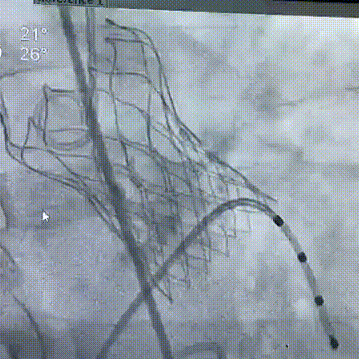

瓣膜定位释放

瓣膜释放后造影

快速起搏下球囊预扩

最终结果

跨瓣压差从术前的58 mmHg,下降到术后的7mmHg